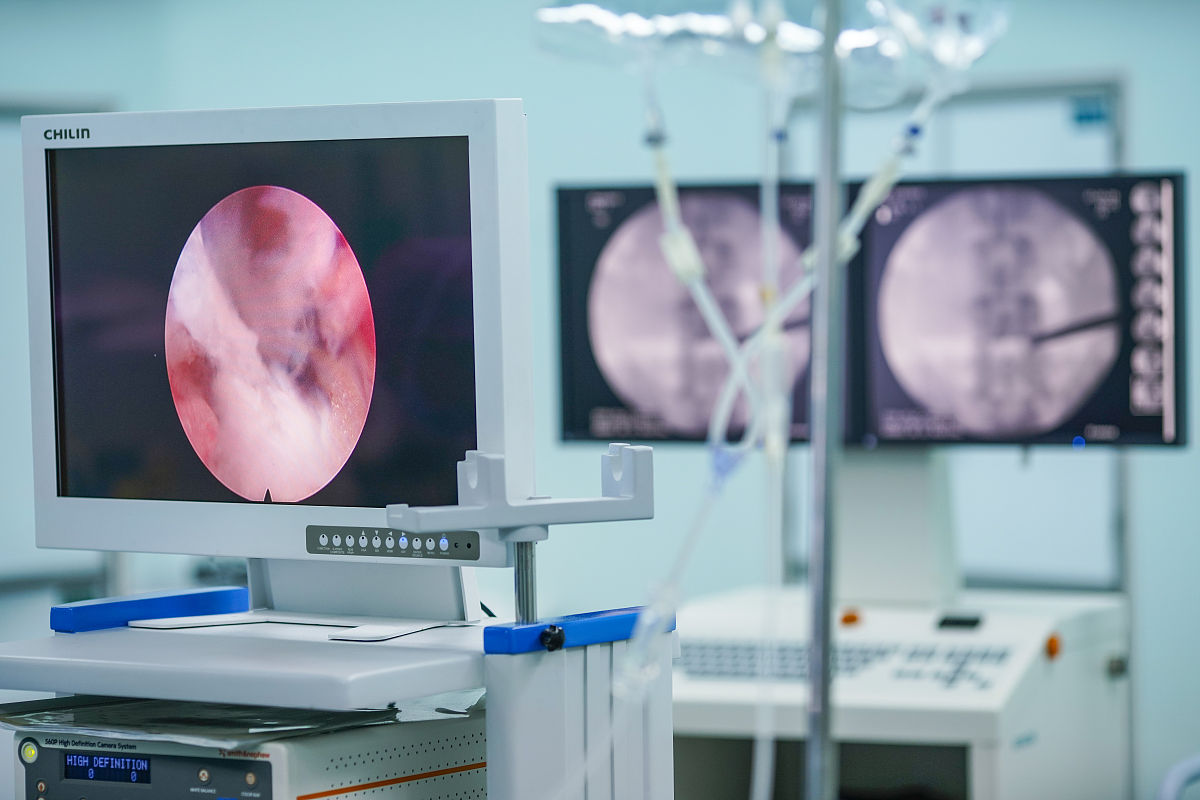

手术过程曲折而充满挑战。首先,医生需要准确地定位胰腺囊肿的位置和大小。通过精密的超声内镜引导技术,医生们成功地完成了囊肿的定位和评估。然而,困难并未结束。胰腺囊肿的穿刺过程需要极高的技术要求和精准的手眼协调能力。医生们紧张而稳定地操作,最终成功地完成了穿刺。

接下来,最具挑战性的环节来临——双蘑菇头全覆膜金属支架的置入引流。这项技术需要医生们仔细选择支架的尺寸和型号,确保其完全适应患者的囊肿。一丝差错都可能导致手术的失败。然而,这个团队在紧迫的情况下,展现出了高超的技术和冷静的思维。他们无畏地面对挑战,成功地将双蘑菇头全覆膜金属支架置入囊肿,实现了引流和排液的目的。